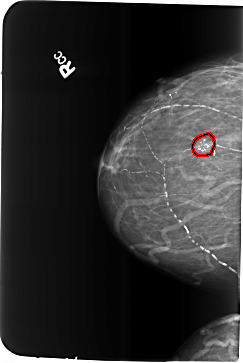

B_3481_1.RIGHT_MLO

RIGHT_MLO LINES 5728 PIXELS_PER_LINE 3976 BITS_PER_PIXEL 12 RESOLUTION 50 OVERLAY

FILE: B_3481_1.RIGHT_MLO.OVERLAY

TOTAL_ABNORMALITIES 1

ABNORMALITY 1

LESION_TYPE CALCIFICATION TYPE COARSE-PLEOMORPHIC DISTRIBUTION CLUSTERED

ASSESSMENT 2

SUBTLETY 5

PATHOLOGY BENIGN

TOTAL_OUTLINES 1

BOUNDARY